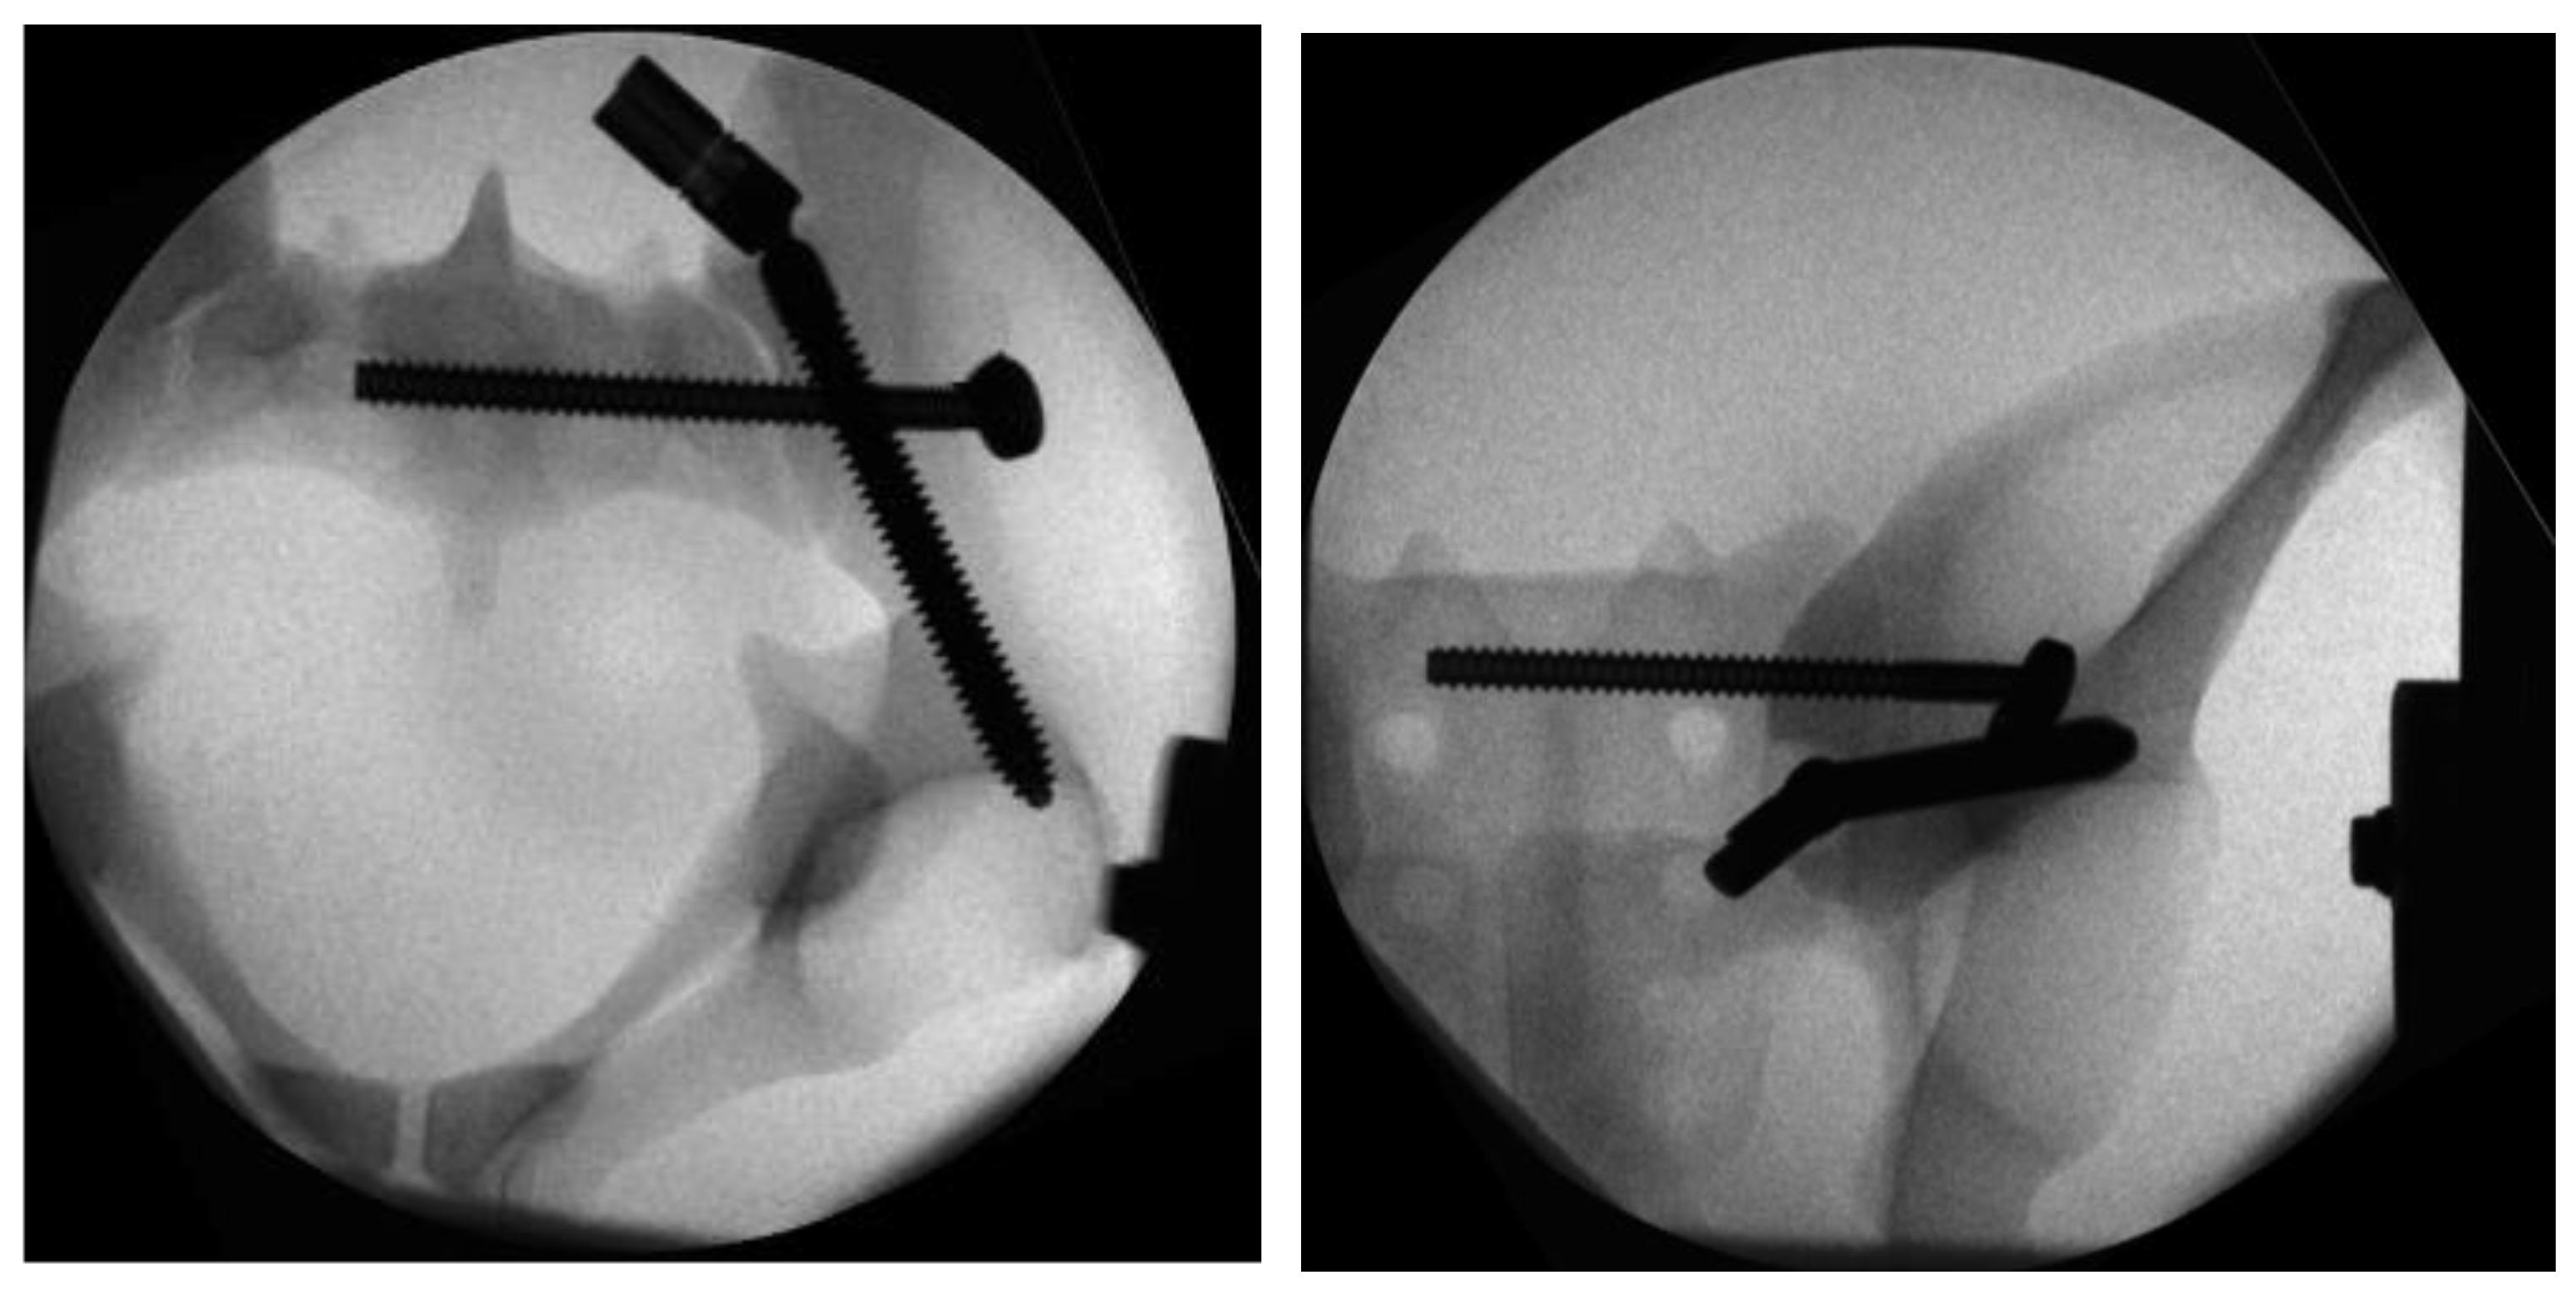

In Group II, the instrumentation was similar to Group I. First, the iliac screw was placed as described. The main difference was in the placement of the sacroiliac screw that was placed separately without the use of the aiming device of Group 1. The guiding wire for the iliosacral screw was placed under radiographic control using a custom-made drill guide. The iliosacral screw was placed next to the iliac screw in a more cranial position to the iliac screw (Figure 4).

Figure 4.

Radiographs in two planes of the conventional triangular fixation with the sacroiliac screw separate from the iliac screw in a more cranial position.